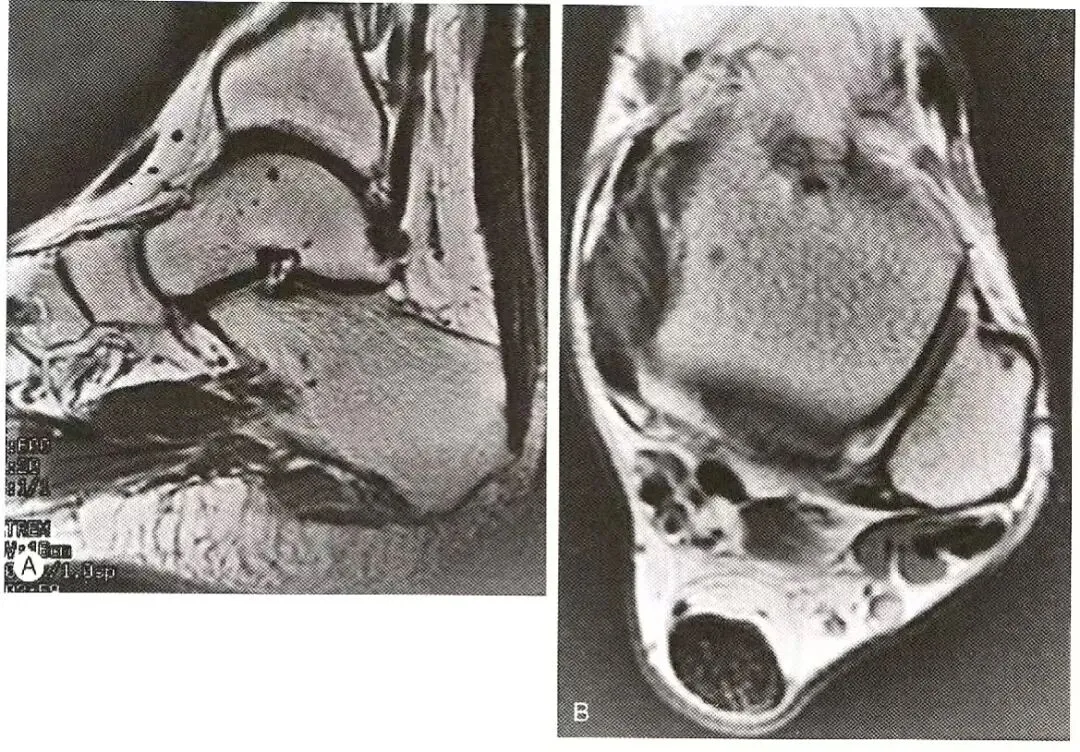

胫后肌腱(T)轻度增粗,信号强度正常,周围充满高信号液体。